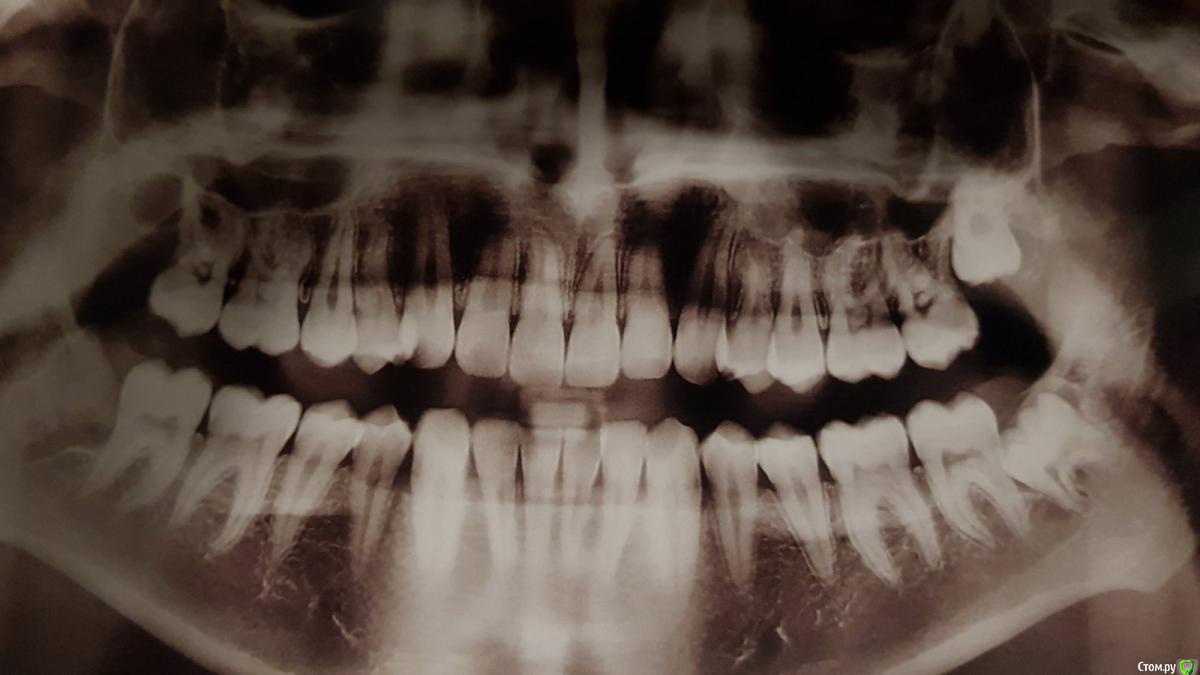

It'sGeorgy Опубликовано 30 мая, 2020 Поделиться Опубликовано 30 мая, 2020 (изменено) Подниму тему, чтобы лишний раз не создавать.Подскажите пожалуйста, вчера впервые столкнулся с новым для себя строением верхних восьмерок. Снимок беды не предвящал. На практике оказались небный и сросшиеся щечные. Апекс небного выраженно загнут щечного, апекс щечного загнут небно, между этими загибами 2-3 мм. костной ткани. Попытался изначально покачать элеватором - почти ноль эффекта. Взял щипцы, попробовал вестибулярно качнуть - так же ноль эффекта. Распилил по горизонтали, элеватор в распил, крутанул - хрусть получен. Взял иглодержатель, проверил, разделены ли до конца корни - разделены, можно было немного пошатать каждый раздельно, трещина уходящая вглубь фуркации так же визуализировалась. А вот в дальнейшем у меня ушло минут 40 для того, чтобы вытащить эти корни, ибо они как стояли намертво до распила по фуркации, так и остались стоять после него. Вытащил апексы путем выпиливания кости вокруг, предварительно отломав процентов 70 от длинны корней. Спасибо моей пациентке, что на протяжении часа с лишним могла держать широко рот и моему налобнику, который в тяжелой ситуации помог сохранить визуализацию, без этого совсем тяжко было бы. Вопрос такой: что делать, с такими зубами, когда ты уже фрагментировал корни, а они все еще неподвижны? Сразу пилить вокруг? Или был шанс их вывихнуть без выпиливания и у меня просто не получилось? Изменено 30 мая, 2020 пользователем It'sGeorgy 1 Ссылка на комментарий

kramer Опубликовано 30 мая, 2020 Поделиться Опубликовано 30 мая, 2020 всегда помогает?Как правило. Очевидно, что верхние 8 почти всегда удаляются быстро. Если по-быстрому не получается, надо прикинуть, в чем может быть причина. Либо это многокорневой зуб, либо загнутые корни, либо мощный бугор (как на вашем снимке), либо комбо. Резекция кости вестибулярно и дистально по крайней мере создаст пространство для вывихивания Ссылка на комментарий